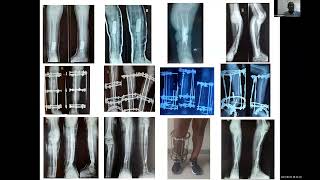

Session 15: Congenital, Developmental, Post Traumatic, Post Infectious Lower Limb Deformity Cases  |   Sanjeev Sabharwal, MD, MPH  |   December 12, 2025  |   24:19

This video is part of the of the 2023 IGOT Limb Differences Webinar. To find the rest of the sessions, please visit the playlists here. You can also find more of Global HELP’s content by visiting the Global HELP YouTube channel.

Session 15: Congenital, Developmental, Post Traumatic, Post Infectious Lower Limb Deformity Cases

Sanjeev Sabharwal, MD, MPH